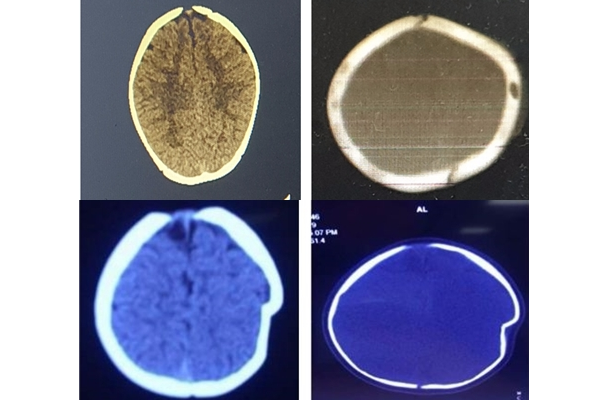

Hộp sọ bé gái 8 tháng tuổi bị lún sâu vì ngã xe tập đi

Trong lúc ngồi một mình trên xe tập đi, không may dây buộc đứt, chiếc xe từ bậc thềm lao xuống sân khiến em bé 8 tháng tuổi bị lún sọ não.